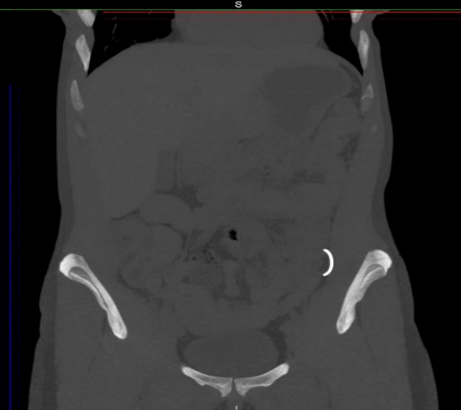

Компьютерная томография.

Позволяет достоверно выявить инородное тело в анатомически сложной области, оценить степень изменений в окружающих тканях, взаимоотношение инородного тела с прилежащими органами, а также выявить наличие возможных осложнений.

Метод выбора для выявления госсипибомы - КТ. В раннем послеоперационном периоде госсипибома наиболее достоверно диагностируется при визуализации округлого образования с губчатой внутренней структурой, с множественными пузырьками газа в структуре. При в/в контрастировании визуализируется тонкое периферическое кольцо контрастного усиления, соответствующее гранулематозному воспалению вокруг инородного тела. В позднем послеоперационном периоде госсипибома может утратить губчатую структуру и КТ-картина может быть сходна с ограниченным скоплением жидкости или с абсцессом. В отдаленном послеоперационном периоде госсипибому следует дифференцировать с новообразованиями, при этом отмечается отсутствие достоверного накопления контрастного вещества как в центральной зоне, так и стенке госсипибомы. В позднем и отдалённом постоперационном периоде также возможна кальцификация стенок госсипибомы.